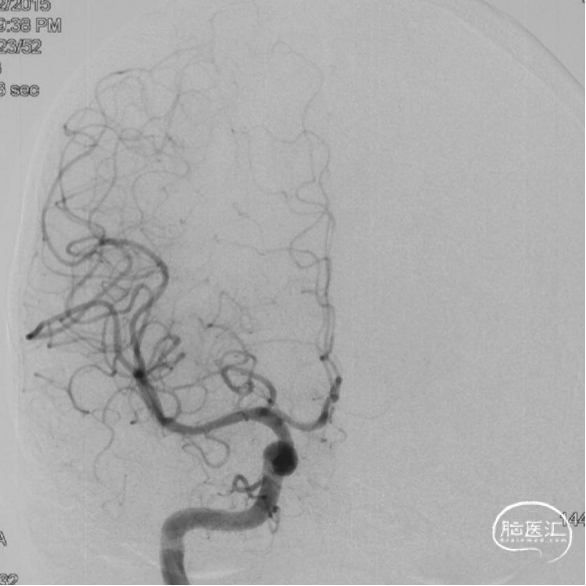

术前造影

双侧颈内动脉正侧位造影见前颅窝底硬脑膜动静脉瘘,双侧筛前动脉、筛后动脉向瘘口供血,通过皮层静脉向上矢状窦引流。

双侧颈外动脉正侧位造影见镰前动脉向瘘口供血。

左侧椎动脉正侧位造影未见明显异常。